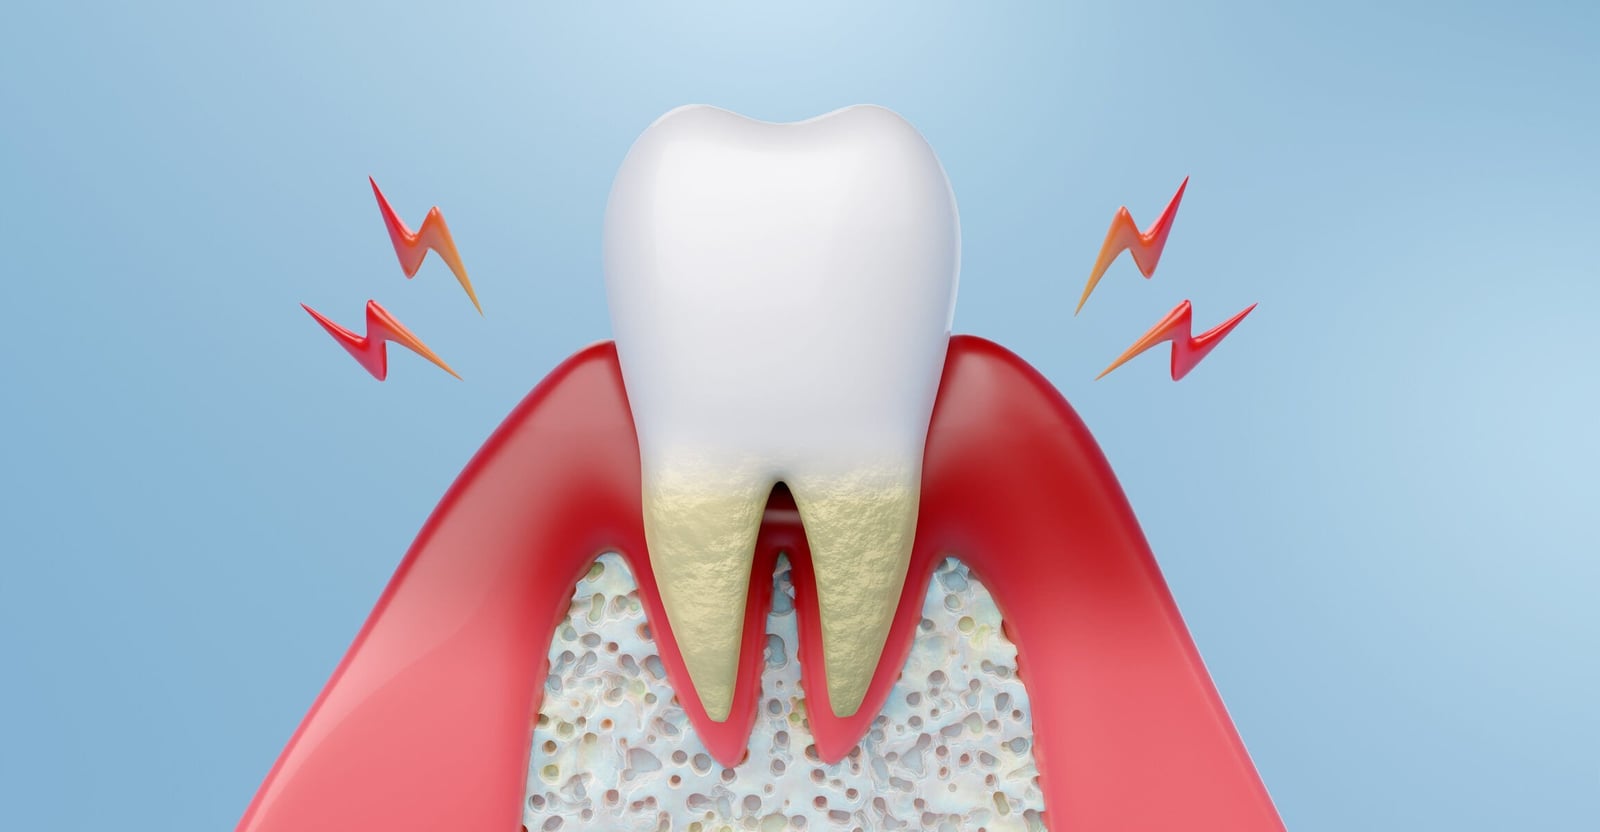

Periodontal disease begins when dental plaque, a sticky biofilm of bacteria that accumulates on teeth, provokes inflammation of the gingiva; if plaque and calculus are not removed, the inflammatory response can extend into the supporting tissues (periodontal ligament and alveolar bone), producing pocket formation, attachment loss, and bone resorption.

Plaque‑induced infection is the central driver, but disease expression depends on the balance between microbial challenge and the host’s immune response—some people develop only reversible gingivitis, while others progress to destructive periodontitis.